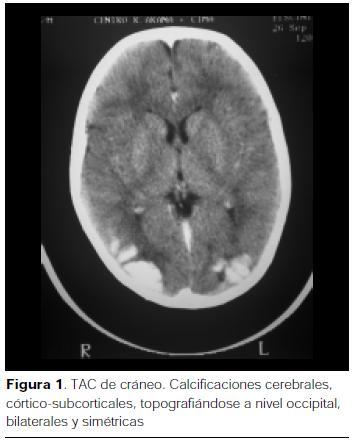

Resonancia nuclear magnética (RNM) de cráneo: evidencia dos áreas en espejo de anomalía focal cortical témporo-occipital. No pudiendo evidenciarse las calcificaciones (figura 2).

En cuanto a las calcificaciones cerebrales, son cortico-subcorticales, serpinginosas, en forma de guirnalda, con doble contorno, topografiándose a nivel parieto-occipital. Típicamente bilaterales y simétricas, electivamente visibles en la TAC de cráneo, tal lo evidenciado en nuestro paciente, no siendo realzadas por medio de contraste intravenoso (1,2,7,8).

Como se observó en nuestro caso, la RNM de cráneo no logra ponerlas en evidencia, solamente muestra la desmielinización periférica a dichas calcificaciones (1,8).